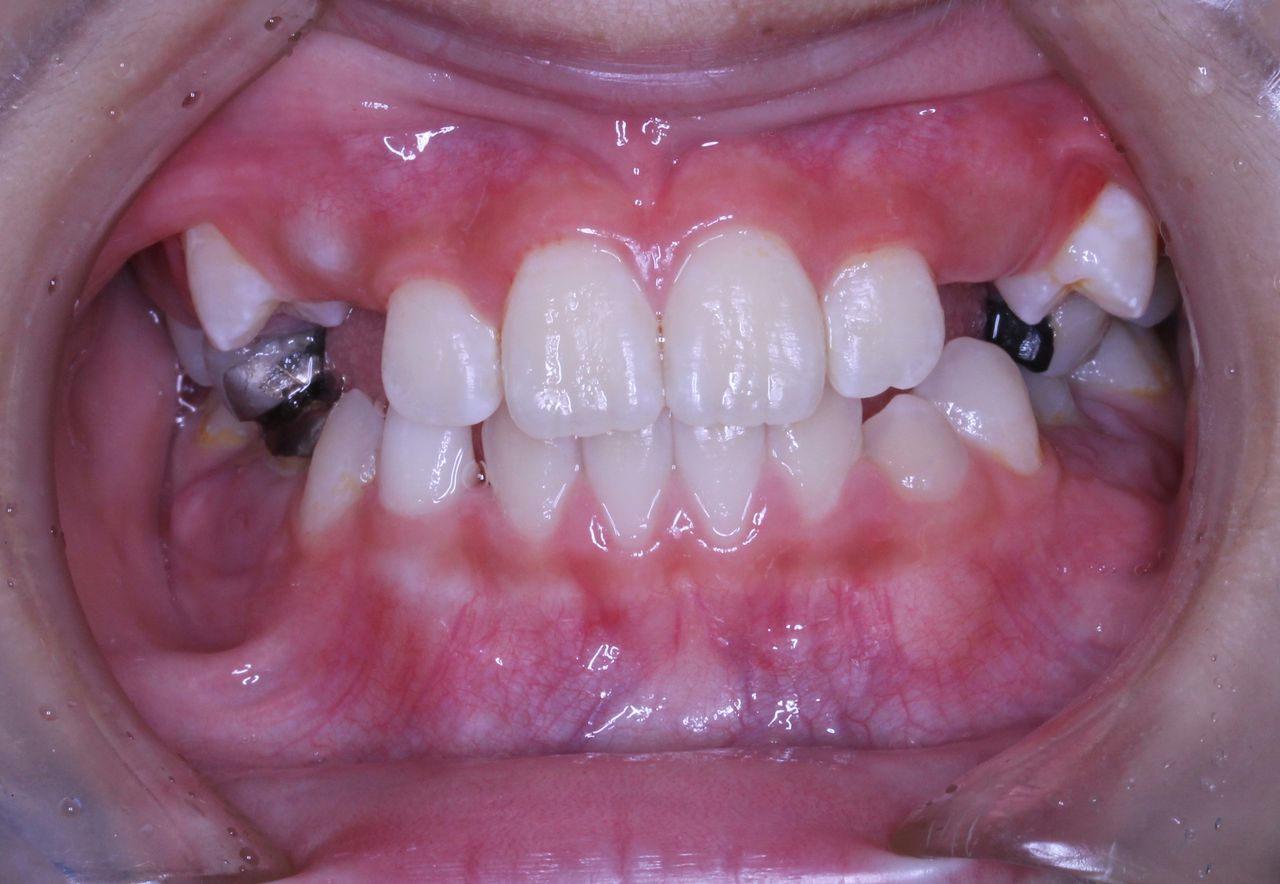

初診時はひどい状況でした。

まず、歯列矯正治療以前に虫歯の管理がまったくされておりませんでした。

年齢は7歳 小学校2年生ですので、 本来なら上下前歯が大人の歯に生えそろい、横の部分は乳歯がすべてある状況です。 いわゆる生えかわりの安定期という時期ですが、この患者さんはすでに何本か乳歯を抜いてしまっております。

また、下の前歯の歯肉も下がってきており、グループ的には1に属するものの、この悲惨は口腔内環境下では、矯正治療をおこなっても散々な結果になることが予想されました。